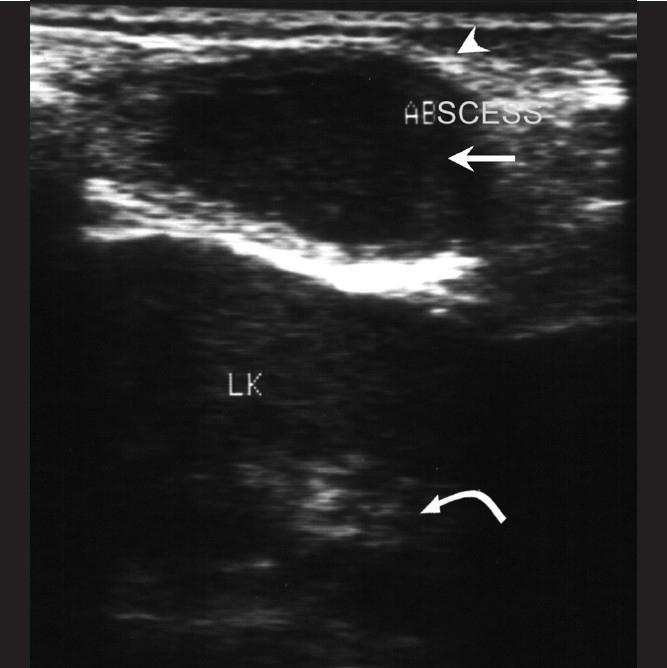

All patients had clinical signs and symptoms localized to the site of involvement, whether it was the sternum, sternoclavicular joints, or ribs. CT scan revealed sternal destruction in three patients and osteolytic lesions with sclerosis of the articular surfaces of the sternoclavicular joints in two patients. In five patients with rib lesions, USG elegantly demonstrated the bone destruction underlying the cold abscess. All cases were confirmed to be of tuberculous origin by pathology studies of the aspirated/curetted material, obtained by CT / USG guidance.

Tuberculous etiology should be considered for patients presenting with atypical sites of skeletal inflammation. CT scan plays an important role in the evaluation of these patients. However, the use of USG for demonstrating rib destruction in a chest wall cold abscess has so far been under-emphasized, as has been the role of CT and USG guided aspiration in confirming the aetiology.

所有患者的临床体征和症状均局限于受累部位,无论是胸骨、胸锁关节还是肋骨。CT扫描显示3例患者胸骨破坏,2例患者胸锁关节面出现骨质溶解伴硬化。在5例肋骨病变患者中,超声清晰地显示了寒性脓肿下方的骨质破坏。通过CT/超声引导下获取的抽吸/刮除材料的病理研究,所有病例均确诊为结核起源。

对于出现骨骼炎症非典型部位的患者,应考虑结核病因。CT扫描在评估这些患者中起重要作用。然而,超声在显示胸壁寒性脓肿中肋骨破坏方面的应用至今未得到充分重视,CT和超声引导下抽吸在确诊病因方面的作用也未得到充分重视。